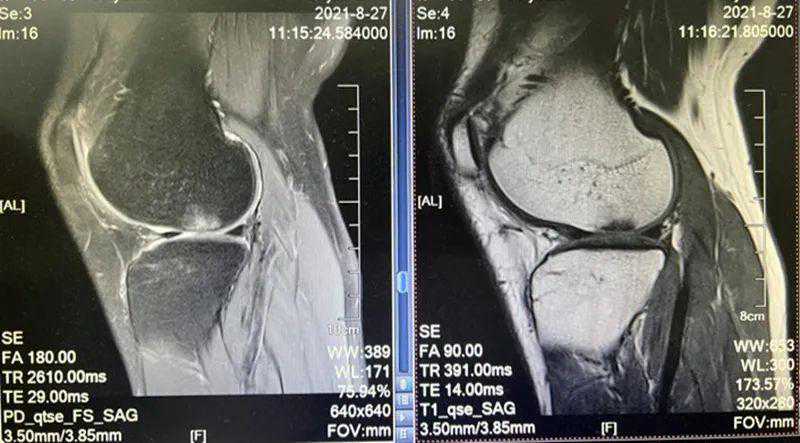

影像学检查:损伤组织定位,组织损伤程度判断